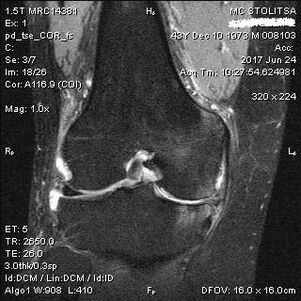

ការធ្វើរោគវិនិច្ឆ័យជម្ងឺរលាកសន្លាក់នៃសន្លាក់ជង្គង់កើតឡើងនៅក្នុងការិយាល័យអ្នកជំនាញខាងជំងឺមហារីកស្បែកឬអ្នកជំនាញខាងឆ្អឹង។ វេជ្ជបណ្ឌិតពិនិត្យមើលការរួមគ្នាដែលរងផលប៉ះពាល់ធ្វើឱ្យវាមើលទៅពាក្យបណ្តឹងនិងសួរសំណួរបន្ថែម។ អនុវត្តការធ្វើតេស្តជាច្រើន - ឧទាហរណ៍ការស្នើសុំឱ្យអ្នកជំងឺពត់ជើងរបស់គាត់ឬដើរពីរបីជំហាន។ បន្ទាប់មកប្រសិនបើចាំបាច់ក្នុងការបញ្ជាក់ពីដំណាក់កាលនៃជំងឺឬធម្មជាតិនៃការផ្លាស់ប្តូររោគសាស្ត្រគាត់នឹងបញ្ជូនអ្នកសម្រាប់ការសិក្សាបន្ថែម។ ឧទាហរណ៍សម្រាប់ការគណនា tomography ឬកាំរស្មីអ៊ីវ។